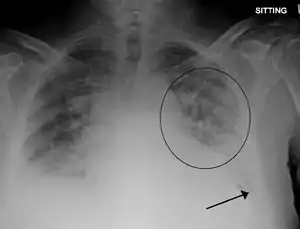

| Pulmonary edema with small pleural effusions on both sides. | |

Low oxygen saturation and disturbed arterial blood gas readings support the proposed diagnosis by suggesting a pulmonary shunt. A chest X-ray will show fluid in the alveolar walls, Kerley B lines, increased vascular shadowing in a classical batwing peri-hilum pattern, upper lobe diversion (increased blood flow to the superior parts of the lung), and possibly pleural effusions. In contrast, patchy alveolar infiltrates are more typically associated with noncardiogenic edema[2]